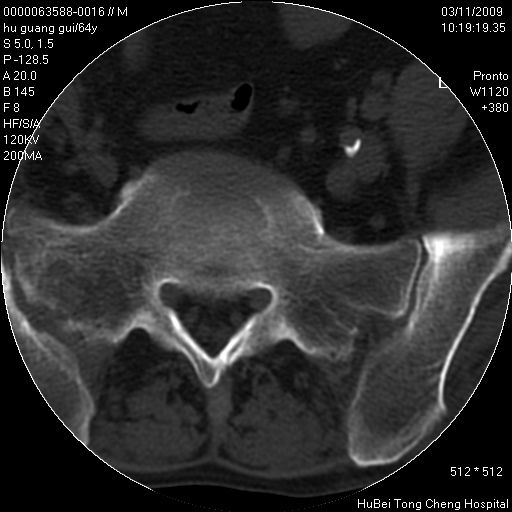

患者 男,64岁。腰痛十余天。(临床未提供其他病史)

临床诊断:腰痛原因待查(腰椎间盘突出症?)。

腰椎间盘ct轴位平扫(层厚5mm,层距4mm),图像如下:

腰椎退行性变,腰4—5椎间盘膨出。

右侧骶骨侧块骨侵蚀,骶髂关节骨性关节面破坏,并见软组织肿块,考虑骨转移瘤可能,进一步检查。

1.腰椎退行性变,腰4—5椎间盘膨出。

2.右侧骶骨侧块骨侵蚀,骶髂关节骨性关节面破坏,并见软组织肿块,考虑:脊索瘤,骨转移瘤可能,进一步检查。

1)腰椎退行性变,l4—5椎间盘膨出。2)骶骨右侧块骨转移瘤可能,3)水平骶椎。建议作一步检查。